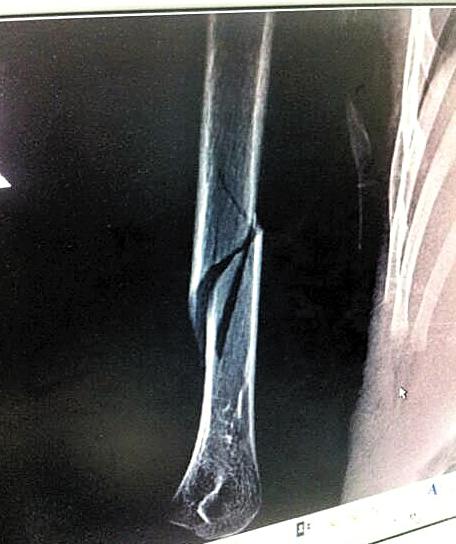

男童骨折照片

4歲的小勁右手打著石膏和夾板,他是位于廣州市蘿崗區(qū)的南方中英文學(xué)校?。?)班的學(xué)生,但已經(jīng)一個月沒有上幼兒園了。原因是7月14日,他的右手上臂被老師弄傷,導(dǎo)致骨折。在廣州市正骨醫(yī)院提供的放射檢查報告單上,可以看見小勁右手上臂骨頭中間有一處明顯斷裂。